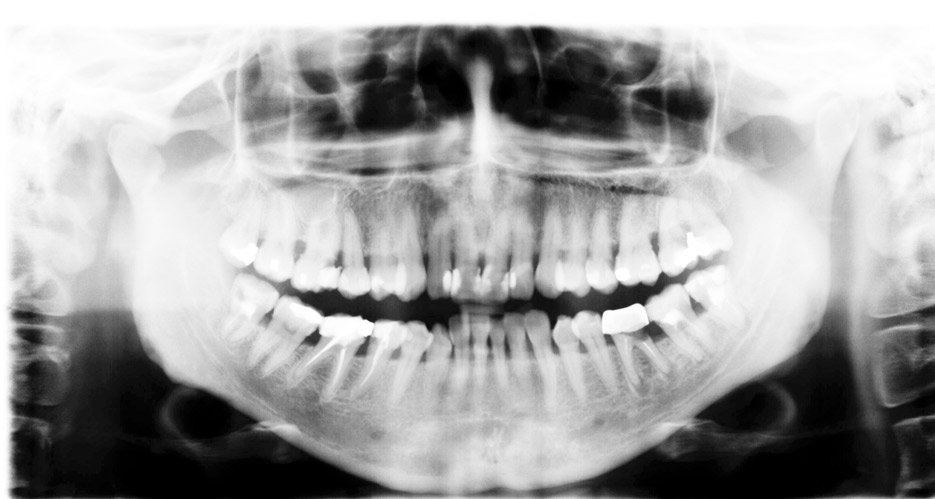

La odontología holística y biológica se basa en la premisa de que la salud dental no puede ser aislada del resto del cuerpo. Por ejemplo, los dentistas holísticos suelen evitar el uso de metales pesados en los tratamientos y, en su lugar, optan por materiales que sean más amigables con el organismo. Esto puede incluir el uso de resinas compuestas o cerámicas que no solo son estéticamente agradables, sino que también minimizan la exposición a sustancias tóxicas.

- Biocompatibilidad: Se utilizan materiales dentales que sean compatibles con el cuerpo, evitando sustancias como el mercurio en empastes y eligiendo alternativas más seguras.

- Materiales Biocompatibles: Utiliza materiales que son no tóxicos y que se integran mejor con el organismo, como resinas compuestas o cerámicas.